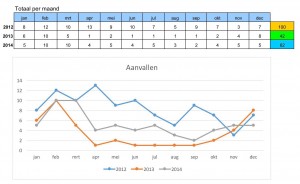

Ik liet hem ook mijn overzicht zien waarop ik bijhoud hoe vaak ik een evenwichtsstoornis heb gehad. Deze waren drastisch afgenomen sinds ik het medicijn Carbamazepine gebruik. Ik gebruik nu twee tabletten per dag (totaal 400 Mg). Dit was een bevestiging voor de Professor dat hij toen de juiste diagnose heeft gesteld en het ziet er veelbelovend uit. Vol trots liet hij het overzicht van mij aan zijn collega dr. Vincent van Rompaey zien. Zij waren beiden even in een juich stemming. Vervolgens heeft Floris nog een gesloten bril op mijn neus gezet en mij in verschillende houdingen gezet, waarbij hij op een scherm kon zien hoe mijn ogen daarop reageren. Daar kwamen geen noemenswaardige dingen uit.

Op dit moment gaat het wel weer redelijk goed en zijn de aanvallen afgenomen. Ik heb de afgelopen periode van 4 weken maar 1 aanval gehad (vorig jaar in dezelfde periode 8). Die ene aanval werd veroorzaakt op een schoolplein waar het een drukte van belang was en de moeders die hun kroost ophalen geen oog voor je hebben en mij bijna omver liepen. Of liep ik ze omver, ik weet het niet meer…..

Het is enige tijd stil geweest op deze blog. Niet dat er niets gebeurt is….De stand van zaken omtrent mijn evenwichtsstoornis (ziekte van Ménière) is dat ik er nog steeds last van heb. In de grafiek is te zien de aanvallen over de afgelopen 3 jaar.

De gelopen periode zijn er weer een aantal onderzoeken geweest m.b.t. mijn evenwichtsstoornissen. Ik ben nu onder behandeling van het UMCG. Het afgelopen jaar (2012) heb ik 100 evenwichtsstoornissen gehad. Dat varieerde van kleine tot grote “aanvallen”. En het gaat gewoon door, want deze maand heb ik alweer 5 aanvallen gehad.

Vandaag ben ik bij de KNO-arts geweest voor controle. Vanaf half januari tot nu heb ik zo’n 40 lichte en 39 zware evenwichtsstoornissen aanvallen gehad. De aflopen maanden is het iets minder geworden. Dit komt omdat ik mij levensstijl aanpas aan de ziekte. Ik ga minder naar activiteiten waarbij veel mensen aanwezig zijn (bv. de stad in of het bezoeken van een festival, de drukte zoveel mogelijk vermijden). Dit houdt dus in dat je wordt beperkt in je omgang. Ook probeer ik (werk) stress zoveel mogelijk te voorkomen, maar dat valt nog niet mee.

Vandaag ben ik bij de KNO-arts geweest voor controle. Vanaf half januari tot nu heb ik zo’n 40 lichte en 39 zware evenwichtsstoornissen aanvallen gehad. De aflopen maanden is het iets minder geworden. Dit komt omdat ik mij levensstijl aanpas aan de ziekte. Ik ga minder naar activiteiten waarbij veel mensen aanwezig zijn (bv. de stad in of het bezoeken van een festival, de drukte zoveel mogelijk vermijden). Dit houdt dus in dat je wordt beperkt in je omgang. Ook probeer ik (werk) stress zoveel mogelijk te voorkomen, maar dat valt nog niet mee.

Vandaag ben ik bij de KNO-arts geweest voor controle. Vanaf half januari tot nu heb ik zo’n 40 lichte en 39 zware evenwichtsstoornissen aanvallen gehad. De aflopen maanden is het iets minder geworden. Dit komt omdat ik mij levensstijl aanpas aan de ziekte. Ik ga minder naar activiteiten waarbij veel mensen aanwezig zijn (bv. de stad in of het bezoeken van een festival, de drukte zoveel mogelijk vermijden). Dit houdt dus in dat je wordt beperkt in je omgang. Ook probeer ik (werk) stress zoveel mogelijk te voorkomen, maar dat valt nog niet mee.

Vandaag ben ik bij de KNO-arts geweest voor controle. Vanaf half januari tot nu heb ik zo’n 40 lichte en 39 zware evenwichtsstoornissen aanvallen gehad. De aflopen maanden is het iets minder geworden. Dit komt omdat ik mij levensstijl aanpas aan de ziekte. Ik ga minder naar activiteiten waarbij veel mensen aanwezig zijn (bv. de stad in of het bezoeken van een festival, de drukte zoveel mogelijk vermijden). Dit houdt dus in dat je wordt beperkt in je omgang. Ook probeer ik (werk) stress zoveel mogelijk te voorkomen, maar dat valt nog niet mee.De KNO-arts gaf aan dat er een mogelijkheid is om de oorzaak van Ménière weg te nemen. De oorzaak ligt in het linkeroor. Deze kan “afgesloten” worden, wat inhoudt dat je dan volledig aan dit oor doof bent, terwijl mijn rechteroor qua doofheid het slechts is. Dit is nu bepaald geen optie waar ik blij mee ben. De KNO-arts gaat mij nu doorverwijzen naar het UMCG te Groningen. Daar kan men eventueel na onderzoek een advies geven welke mogelijkheden er zijn om de Ziekte van Ménière zoveel onder controle te krijgen